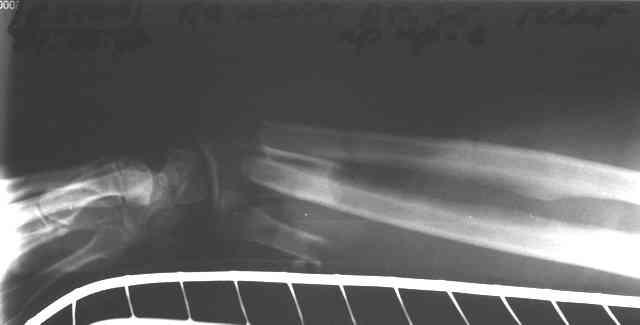

Открытая тяжелая травма предплечья

Травма 24 Октября этого года. Диагноз: Неполный травматический отрыв нижней трети предплечья. Выполнено: ПХО открытого перелома, фасциотомия, ЧКДО, шов лучевой артерии. Размозженые мышцы-сгибатели кисти и пальцев экономно иссечены - не сшивались.

Спустя месяц выполнена резекция 2,5 см некротизированного конца проксимального отломка лучевой кости.

На сегодняшний день по ладонной поверхности предплечья с переходом на наружний край имеется рана с дефектом мягких тканей, выполненная грануляциями с дна и с краев.